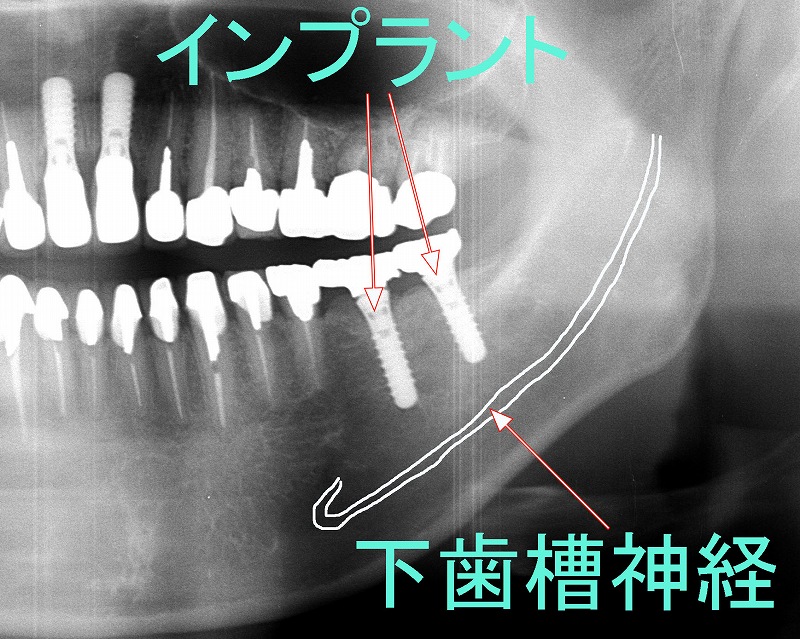

🛠️ インプラント手術

下顎のインプラントでスクリューが神経に接触または侵入すると、知覚異常を引き起こす可能性があります。設計ミスやドリルの誤進入が原因になることも。

🖼️ レントゲン・CT・MRIなどの画像診断

- パノラマレントゲン(全顎撮影)

歯列全体と顎の骨の状態を把握するための基本的な画像です。親知らずと神経の位置関係もおおまかに確認できます。 - 歯科用CT(CBCT)

🔍 術前CT(コーンビームCT)による神経位置の確認

- 下歯槽管の走行・神経と歯根やインプラントとの距離を正確に把握します

- 特に根尖が管に近い親知らずや下顎臼歯部のインプラントは要注意